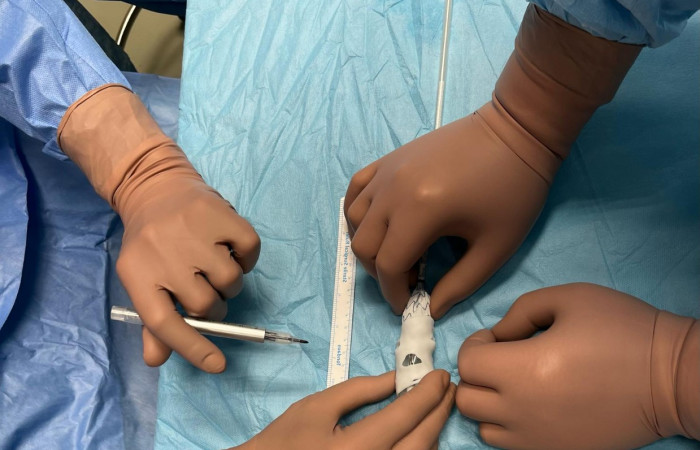

Widoczna na zdjęciach matryca aorty wydrukowana została z żywicy fotopolimerowej, która przeszła proces sterylizacji plazmowej. Użycie technologii 3D umożliwiło indywidualne dostosowanie implantowanego stentgraftu do anatomicznych warunków odejścia naczyń trzewnych od aorty, co z kolei pozwoliło na zakwalifikowanie chorego do małoinwazyjnej procedury zaopatrzenia tętniaka aorty piersiowo brzusznej metodą wewnątrznaczyniową w trybie przyspieszonym.